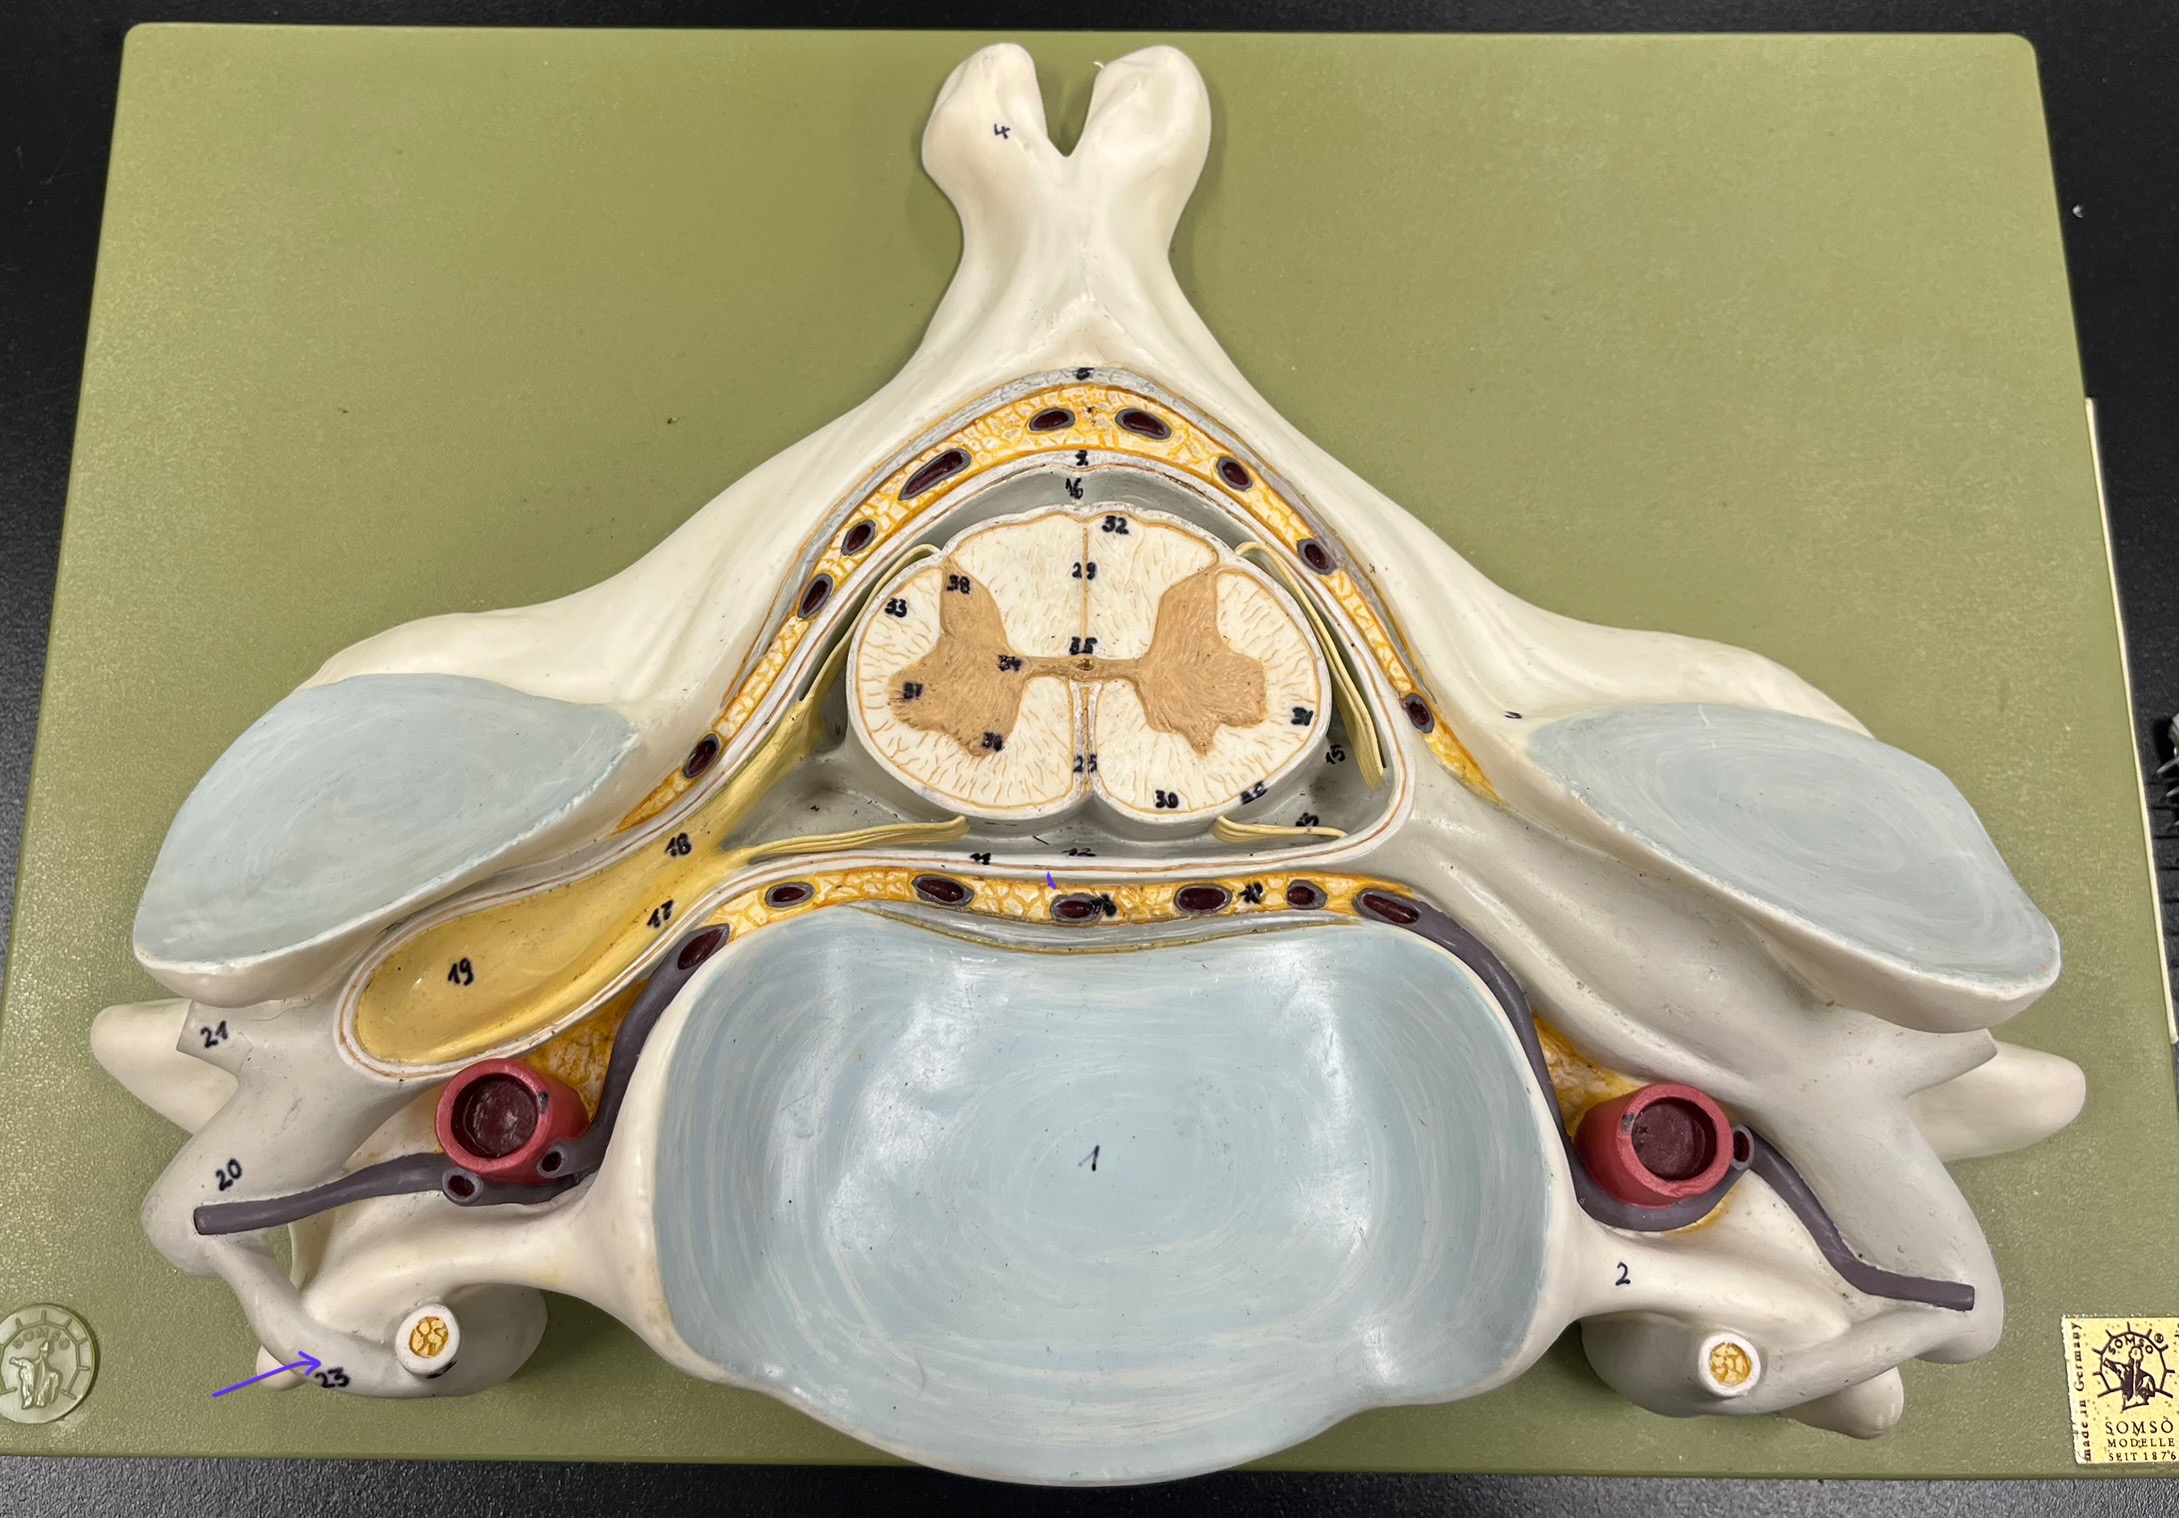

epidural space

dura mater

subdural space

arachnoid mater

subarachnoid space

pia mater

denticulate ligaments

What is the groove here?

anterior median fissure

posterior median sulcus

posterior (dorsal) horn

posterior (dorsal) horn; R—>L

anterior (ventral) horn

lateral horn (selected models)

gray commissure

central canal

anterior column

lateral column

posterior column

white commissure

posterior (dorsal) root ganglion

What is the bulb here?

posterior (dorsal) root ganglion

posterior (dorsal) root

posterior (dorsal) root

anterior (ventral) root

anterior (ventral) root

dorsal ramus

dorsal ramus

ventral ramus

ventral ramus

rami communicantes

rami communicantes

sympathetic chain ganglia

sympathetic chain ganglia